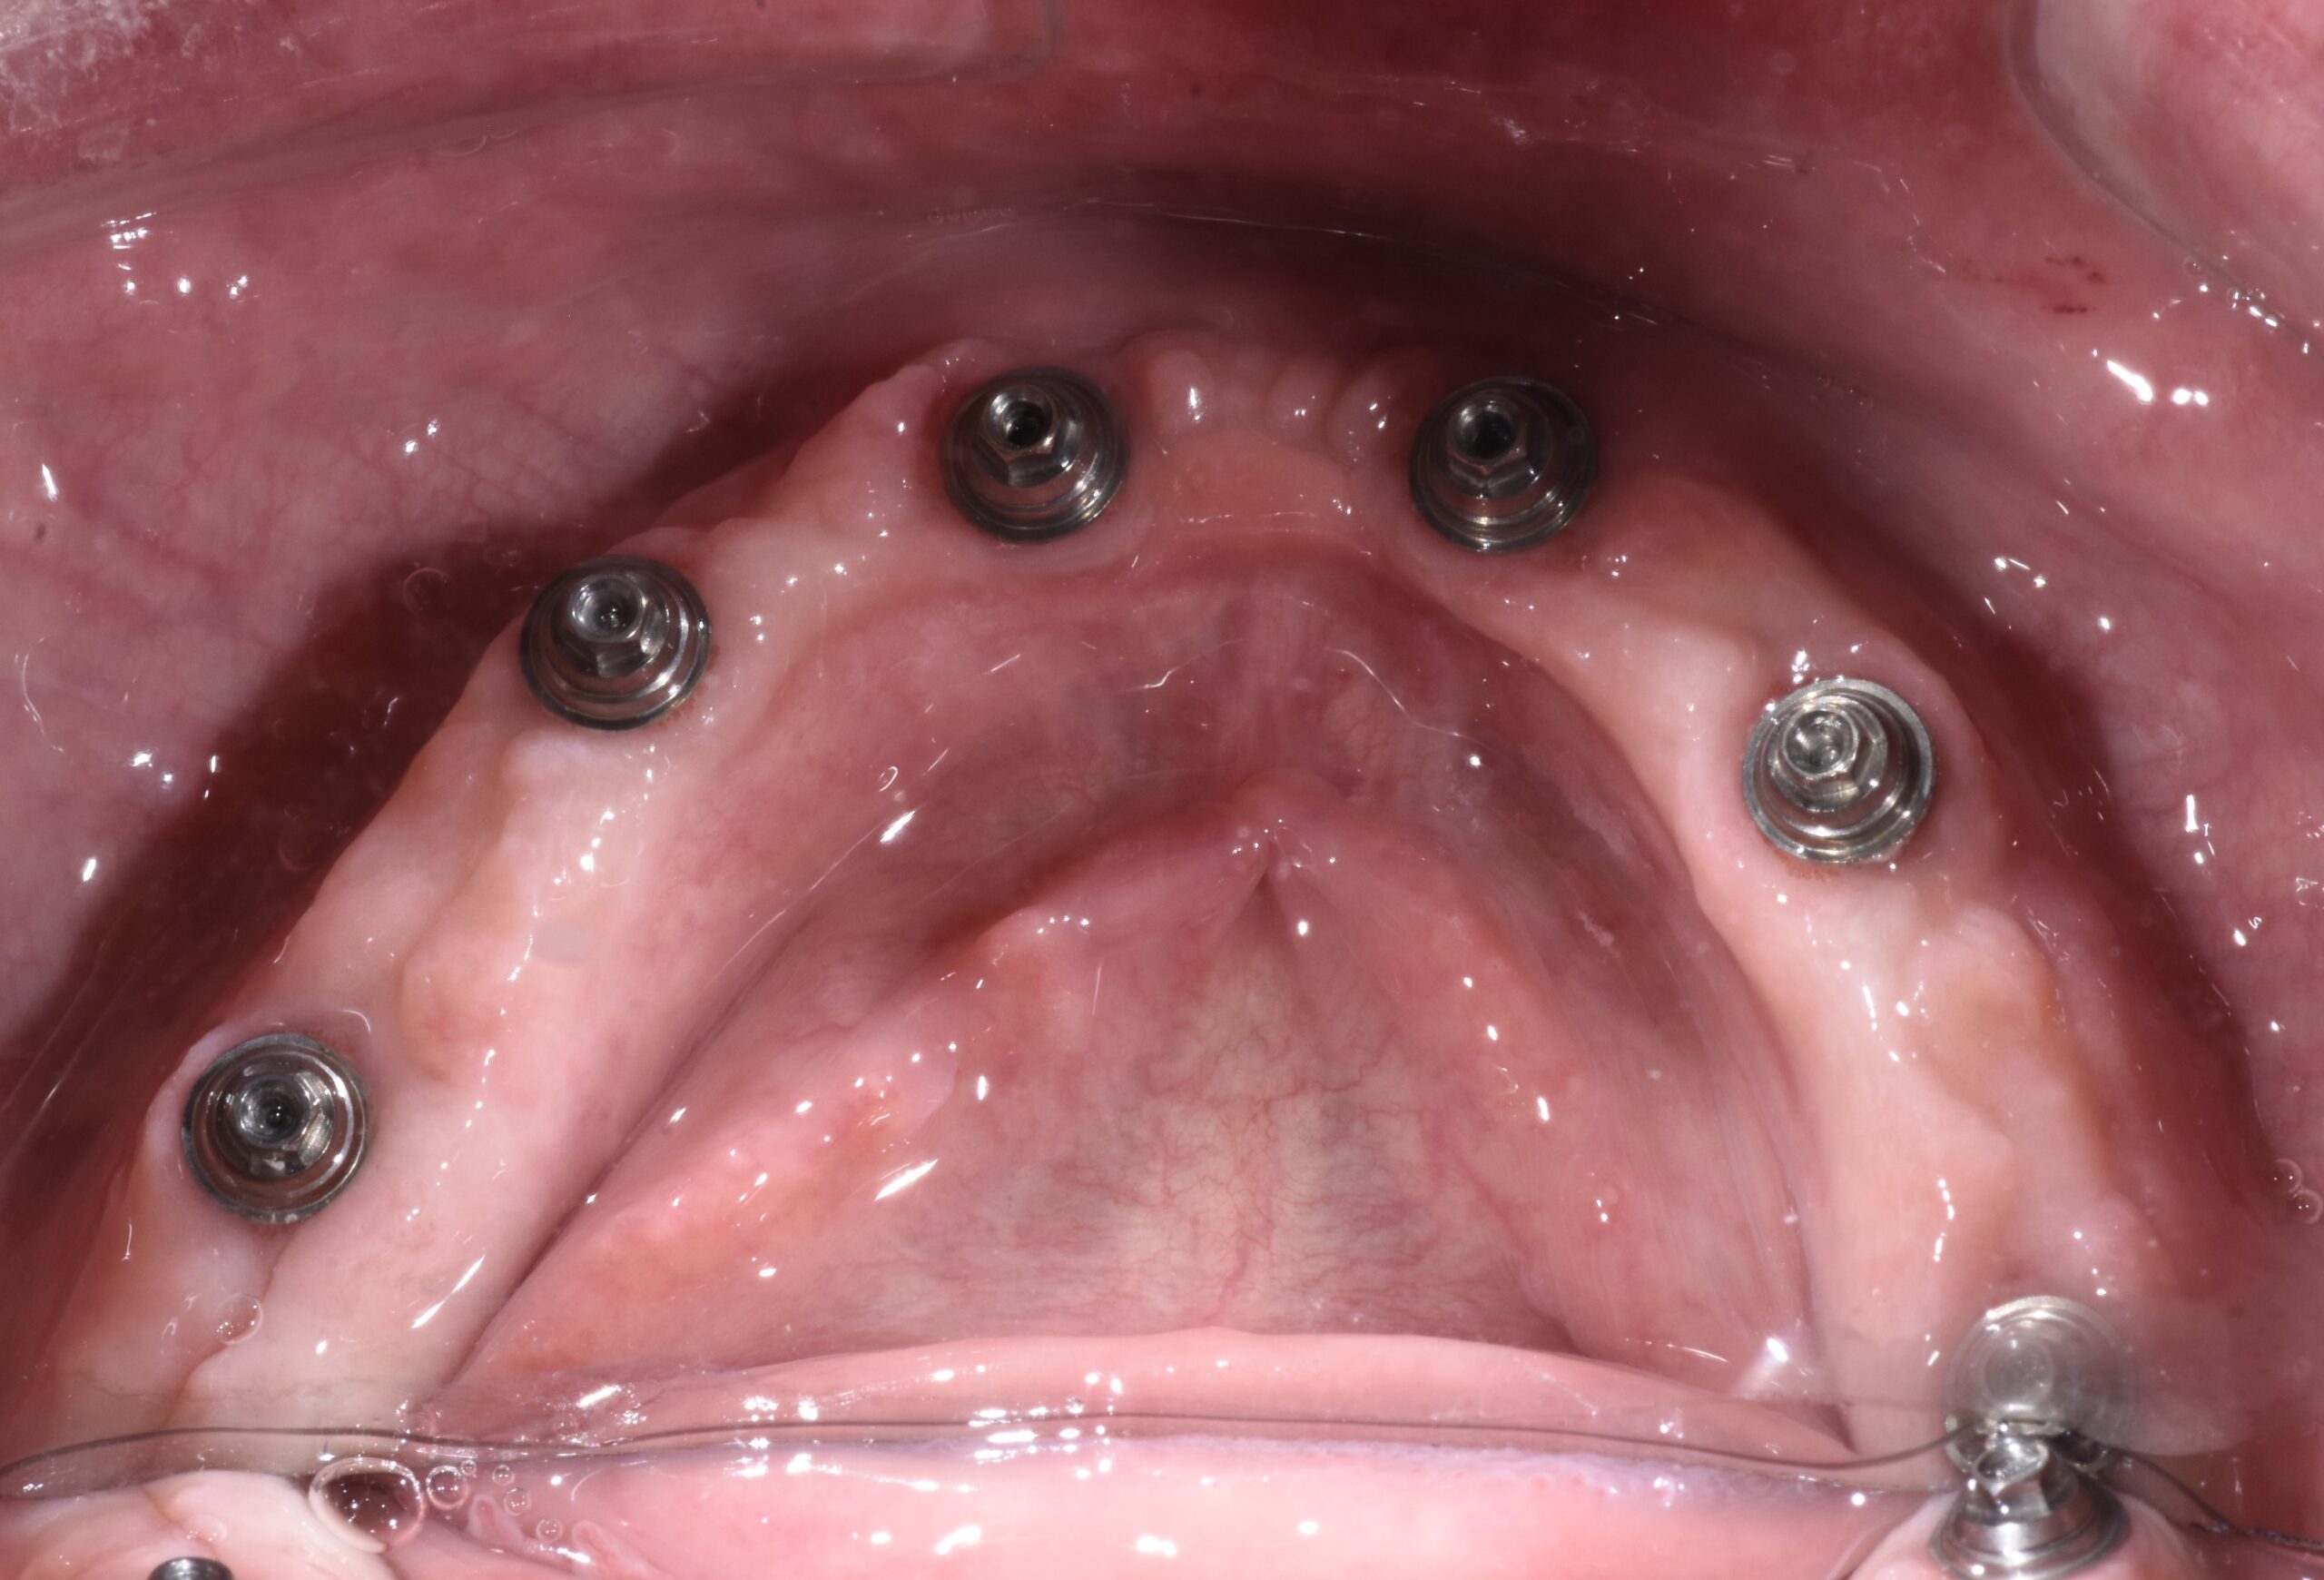

Are you interested in a dental implants to replace a missing tooth, stabilize a denture, or replace multiple missing teeth? Check out our office! Dr. Branson has completed extensive dental implant training. He utilizes a digital approach to pre-plan your surgery, to minimize time in the dental chair, and achieve the best long term result!